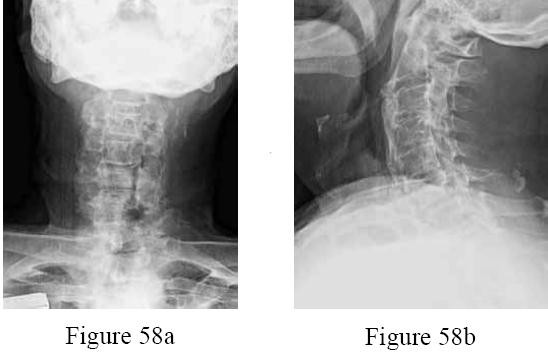

Question 58

A 50-year-old diabetic male presents with severe unremitting back pain. MRI shows findings consistent with L4-L5 discitis and osteomyelitis. He is neurologically intact, hemodynamically stable, and blood cultures are negative. What is the most appropriate next step in management?

Explanation